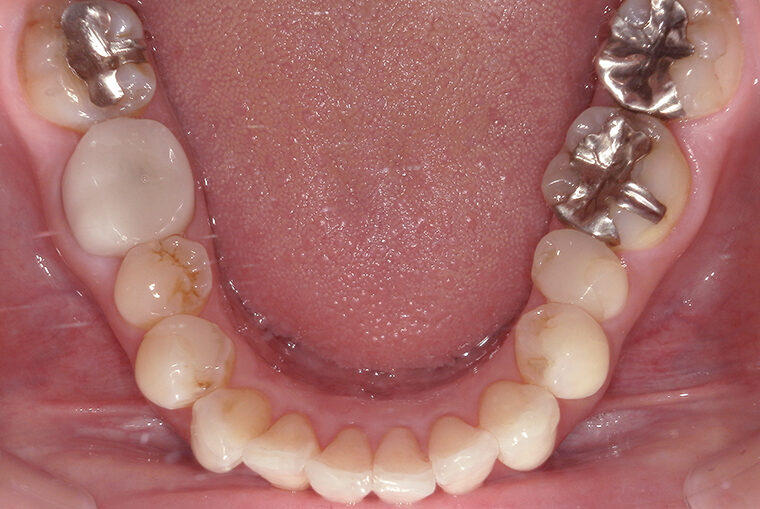

Case Study39歳女性ガタガタな歯のマウスピース矯正-矯正期間9ヶ月